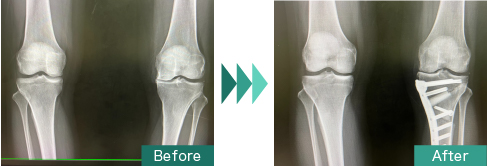

脛骨内側の関節面を開いてO脚をX脚に矯正することで膝の内側への応力の集中を軽減させる方法です。開いた関節面には人工骨を詰めてプレートにて内固定します。

以前はOpening wedge法を採用していましたが近年DTOを積極的に導入しています。

通常は術後1年骨癒合後に抜釘術を施行します。